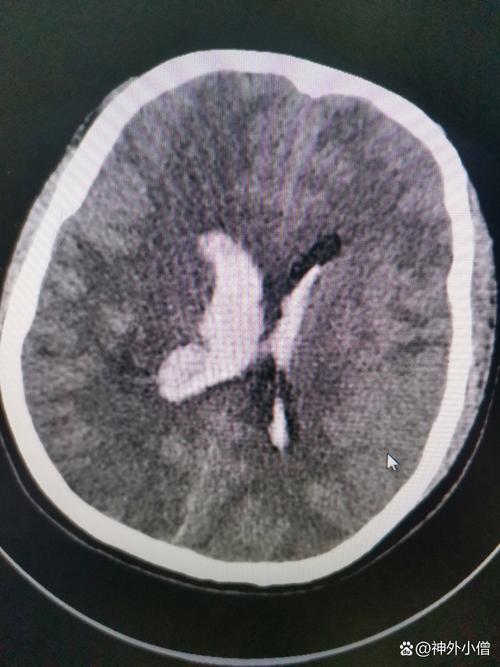

- 脑梗:也叫缺血性脑卒中,是因为脑血管被堵塞,导致脑组织缺血、缺氧而坏死,最常见的堵塞物就是血栓。

堵塞脑血管,引发脑梗:

(图片来源网络,侵删)- 脑动脉的管腔比心脏血管要细得多,当脱落的血栓随着血流到达一个它无法通过的狭窄脑血管时,就会卡住,形成堵塞。

- 被堵塞的脑血管下游的脑组织,瞬间失去了血液供应,氧气和能量耗尽,脑细胞在几分钟内就开始死亡,这就是脑梗。

【重要提示】:由房颤引起的脑梗,通常梗死面积较大,病情更重,致残率和致死率也更高,因为血栓来源较远(从心脏来),溶栓治疗的风险和难度也更大。